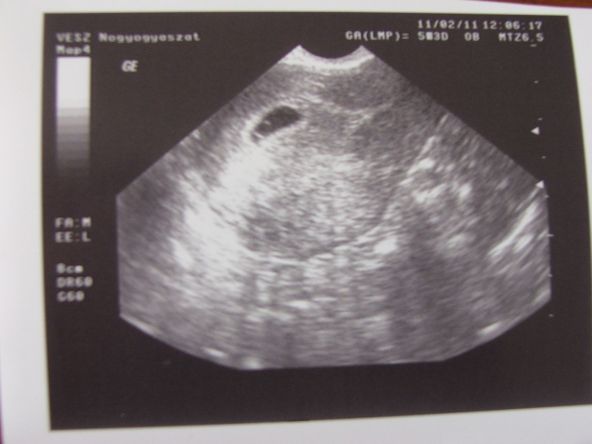

itt a kép..:-)

Kép

Kaqk: :) az en uh-omon is pont egy ilyen pont latszott, fiz ilyen, de jó hogy tettél képet, legalább csodálhatom, én is mintha enyém lenne, kölcsönözhetem néha??

Tegnap voltam uh-n, 7mm-es gestatios gyűrű. Már olvastam itt a fórumon, hogy ez más dokinak is heppje :):):) Doki azt írta, hogy 5hetesnek megfelel a terhesség, és ne nyugtalankodjak (utóbbit szóban:)). Én szikhólyagot és petezsákot vártam... no comment.